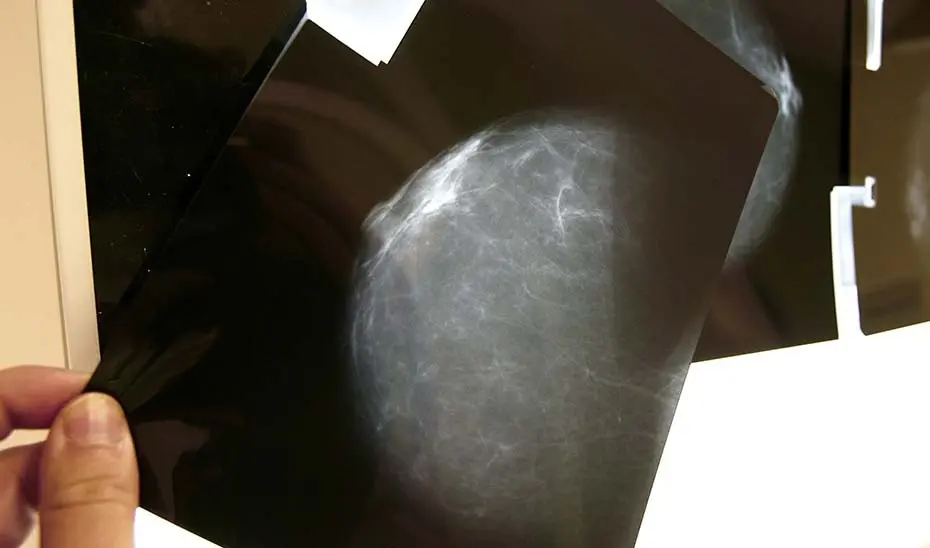

Actualmente, cuando se realiza una mamografía a una mujer dentro del programa de cribado del cáncer de mama existen tres posibles diagnósticos: negativo, positivo y lesión posiblemente benigna.

En el caso de diagnósticos negativos, las pacientes son informadas del resultado; en el caso de diagnósticos positivos, las mujeres son igualmente informadas y derivadas para nuevos procedimientos pero, en los casos en los que se detectan lesiones posiblemente benignas las mujeres pueden no haber sido informadas de que su caso sigue un procedimiento clínico con supervisión médica.

La consejera ha explicado que, en estos casos, hasta tres radiólogos analizan las imágenes y, en función de los factores de riesgo de cada paciente, deciden el tiempo que ha de transcurrir para la segunda prueba. Las pacientes, que viven ajenas a estas circunstancias, reciben al cabo de meses o de un año una llamada que no esperan para esa segunda cita -fijada por el radiólogo- y sienten alarma, intranquilidad y angustia.